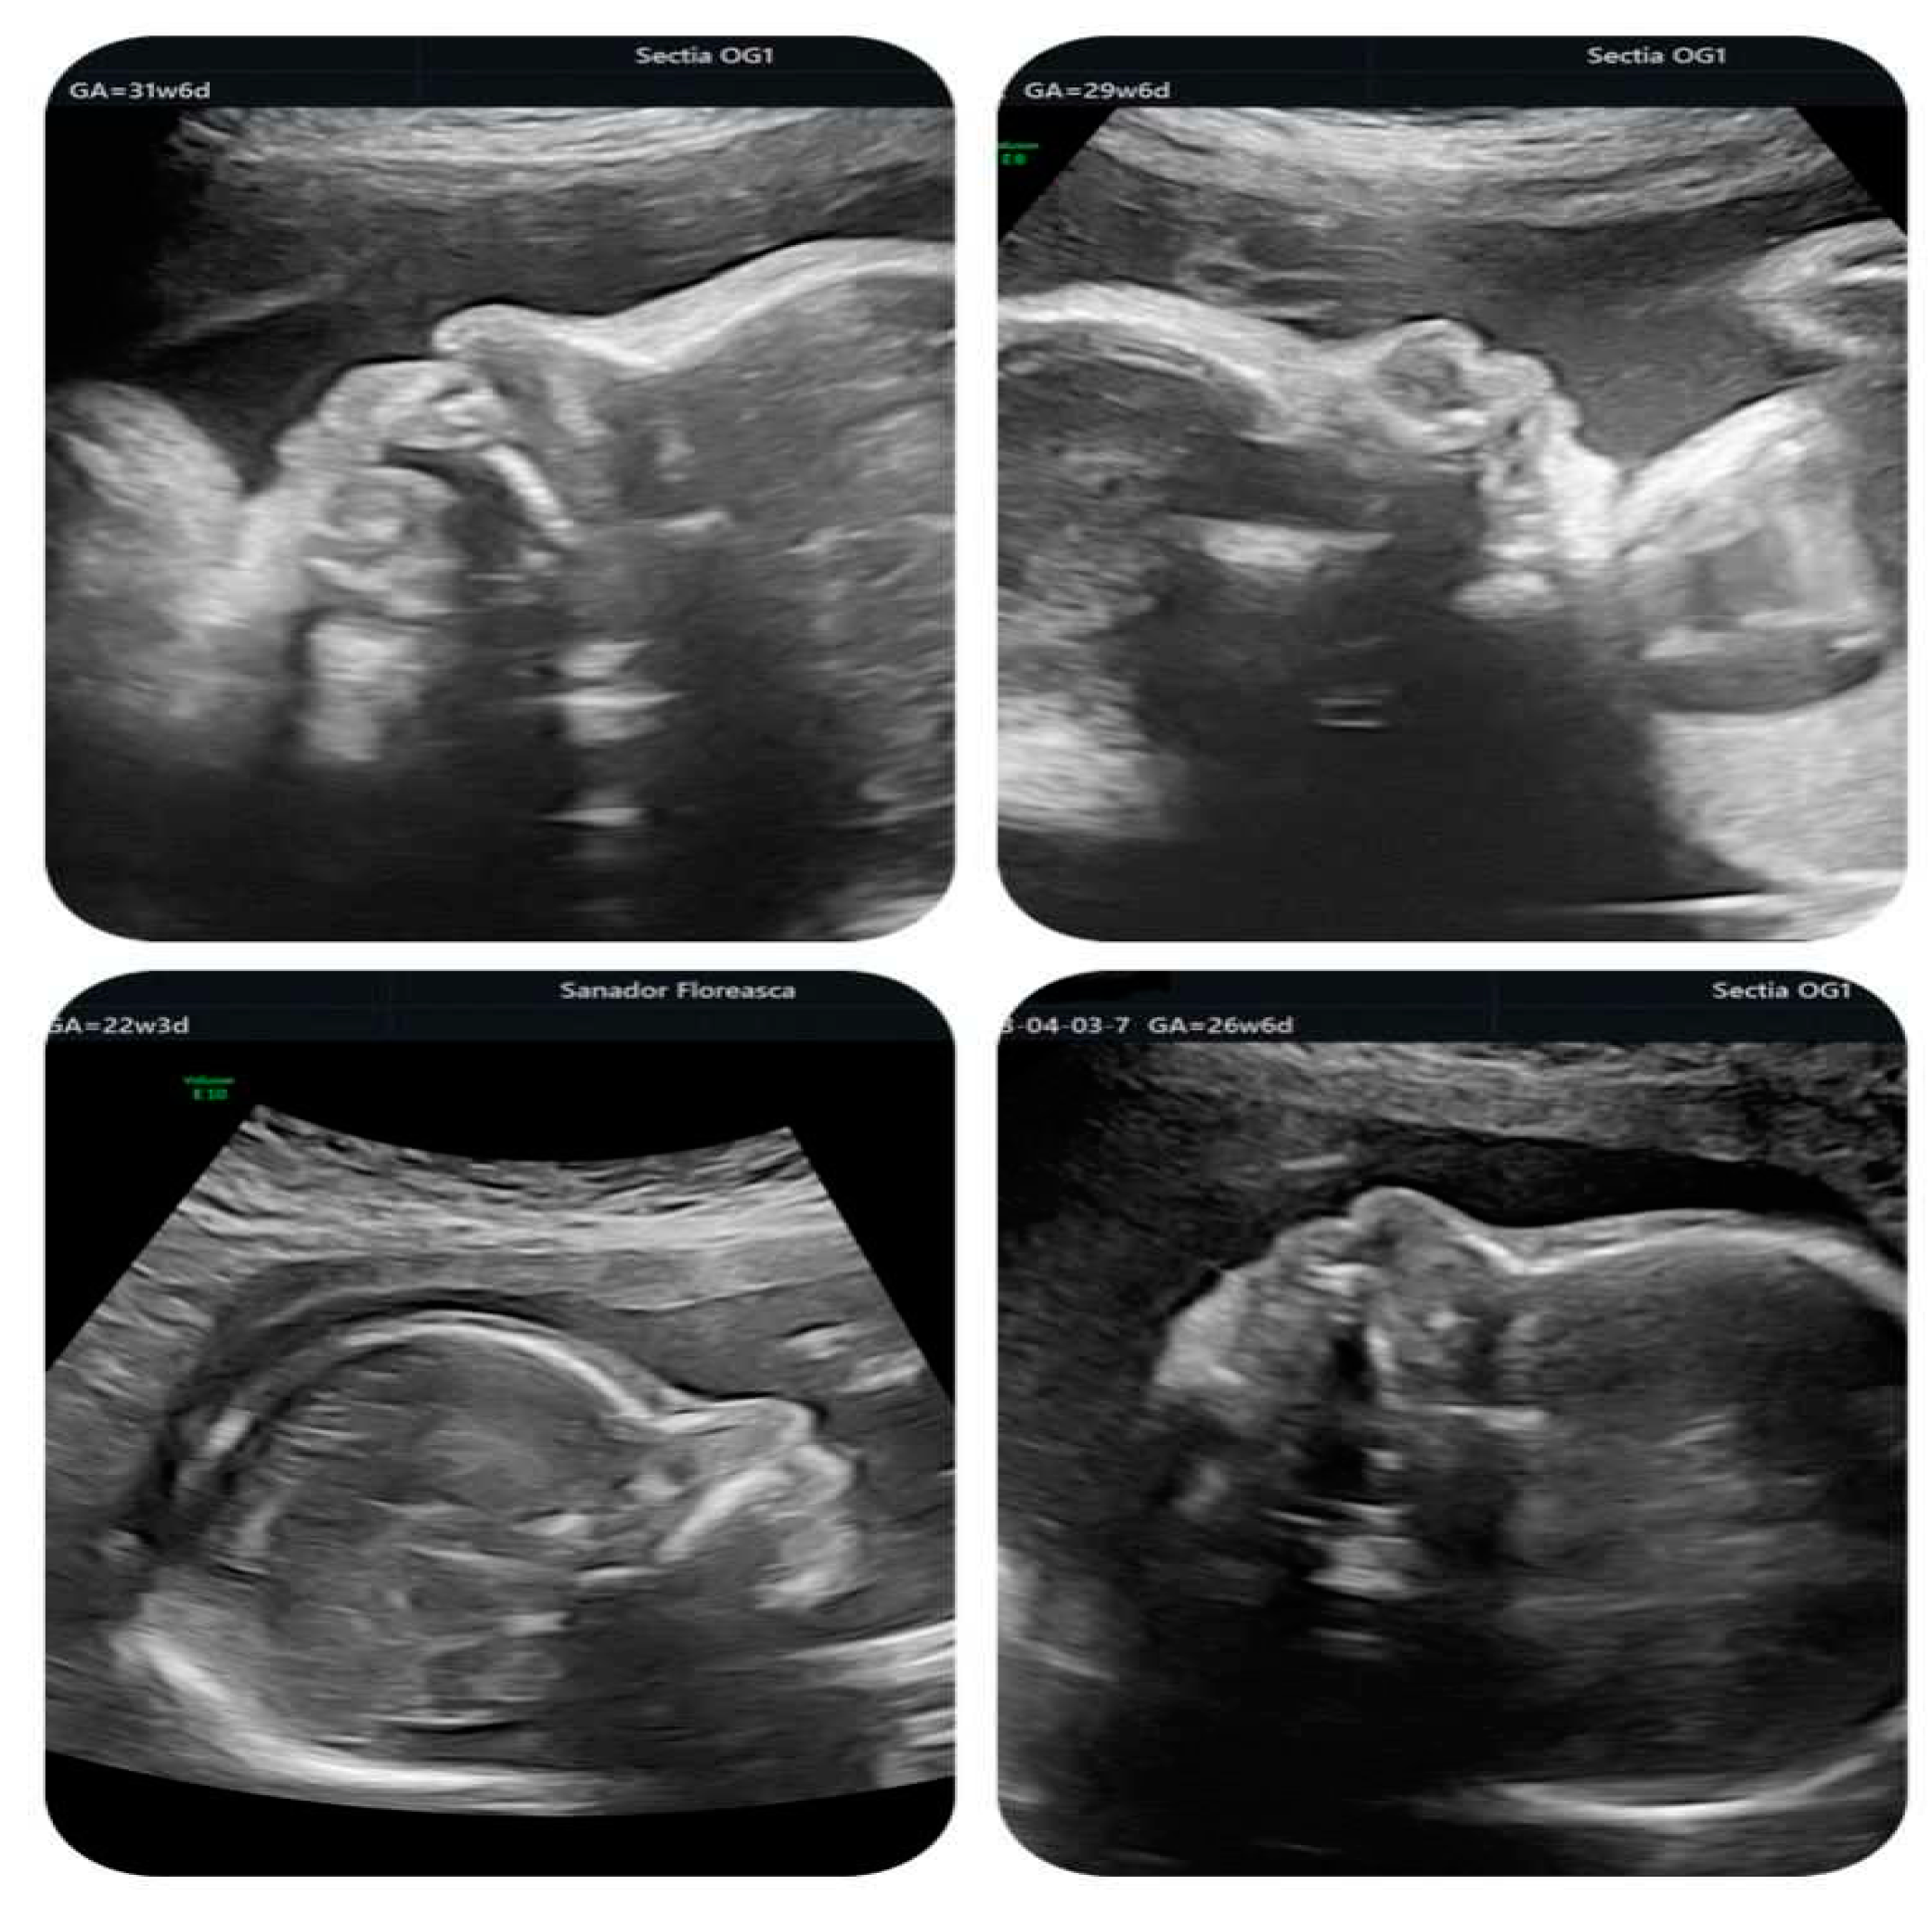

We present the case of a 34-years old IGIP who obtained a spontaneous pregnancy while starting diagnostic work-up for infertility and was examined in our department for the second trimester anomaly scan. The first trimester anomaly scan was reported as normal and she had a low-risk NIPT result for trisomies 21, 18 and 13. Her medical and family history was uneventful. At 22 weeks the ultrasound differential diagnosis of CHD was made between severe aortic coarctation and tubular hypoplasia with VSD and IAA. A dilated pulmonary artery was also revealed. The fetal echocardiography performed by a pediatric cardiologist established the final diagnosis as IAA type B with VSD, pulmonary valve dysplasia and ARSA.

Invasive genetic testing revealed 22q11.2 microdeletion and genetic counselling was offered to the patient who decided to continue the pregnancy. She had regular follow-ups with ultrasound scans every 2-3 weeks to monitor fetal growth and condition and amniotic fluid volume.

In the second half of gestation, we observed an enlarged cavum septum pellucidum (CSP) and polyhydramnios. Extracardiac findings included typical facial features, such as a bulbous nose (